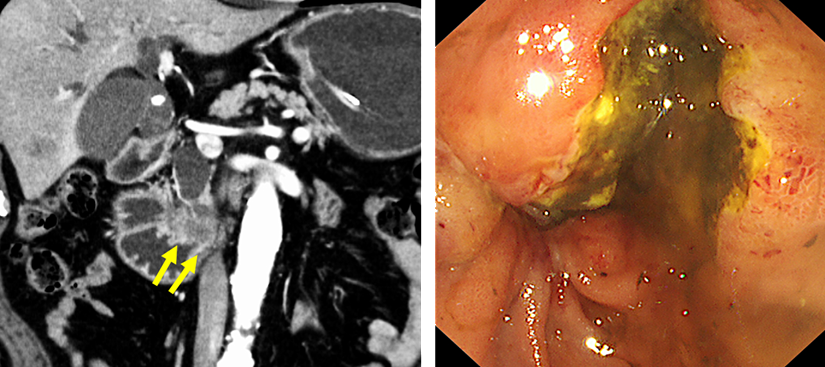

膵頭部癌による閉塞性黄疸と十二指腸狭窄による嘔吐・食事摂取困難を主訴に受診されました。CTでは膵頭部癌の浸潤によって十二指腸の水平部が狭窄(黄色矢印)していました。内視鏡を挿入すると、同部位は高度に浸潤を受けており、嘔吐の原因と考えられました。

十二指腸造影を行い、狭窄部位を確認しました。続いて、狭窄部を十分にカバーするように十二指腸ステントを留置しました。ステント留置後、翌日より食事摂取可能となり、翌々日に退院しました。